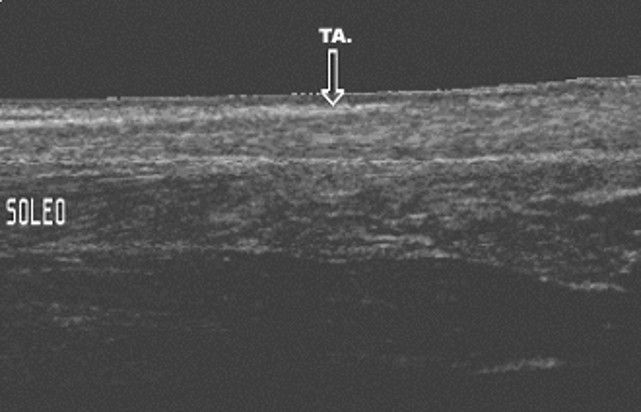

Interpretación especializada del sistema osteomioarticular

Nos enfocamos en la interpretación de ecografías de , tendones, músculos y articulaciones, lo que nos permite detectar con precisión cualquier anomalía o lesión en estas áreas.